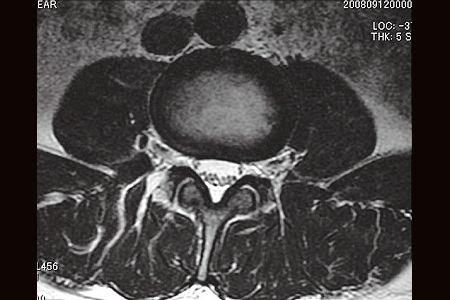

脊柱管狭窄症の診断

- 単純X線(レントゲン)写真である程度は推測できますが、より詳しく診断するためにはMRIや脊髄造影などの検査が必要となります。下肢の動脈がつまって血行障害を生じた時にも似たような症状となることがありますので注意が必要です。

正常な脊惟:横断像

脊柱管狭窄症:横断像

脊柱管狭窄症:矢状断像